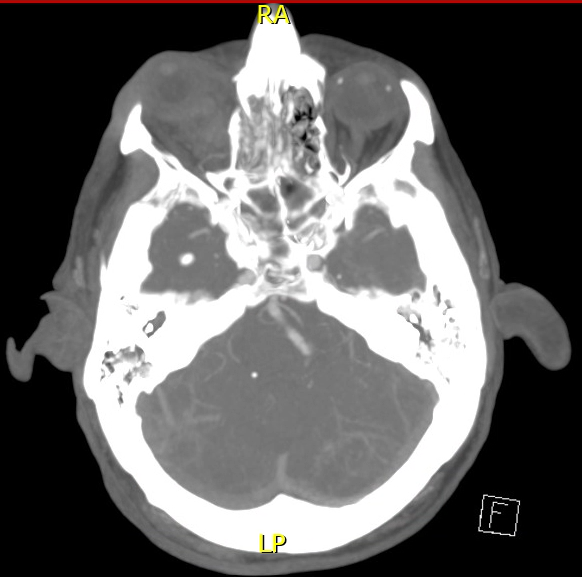

Final CT-Angiogram demonstrating the OAPA noted in in the initial CT-A and angiography, indicating the pseudoaneurysm has most likely self-embolized and no longer taking up any contrast.